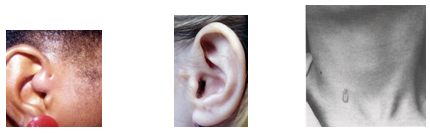

Para se tornar um Cirurgião Pediátrico, o médico precisa fazer dois anos de residência em Cirurgia Geral e mais três anos de residência em Cirurgia Pediátrica, onde verá as diferenças existentes no tratamento dispendidos a um adulto e a uma criança, ganhando habilidade no manuseio desses pacientes tão especiais. Normalmente as cirurgias são mais delicadas, realizadas sob anestesia geral e não necessitam de dormir no hospital (porém muitas delas podem ser realizadas em regime de Hospital Dia com internação que varia de 6 a 12 h). Casos cirúrgicos comuns em crianças são as hérnias inguinal e umbilical, cistos da região do pescoço como os branquiais e o tireoglosso, testículos que não estão situados na bolsa testicular, hipospádia e outras malformações do aparelho urinário, fimose, anquiloglossia (“língua presa”), tumores e doenças gastrointestinais.